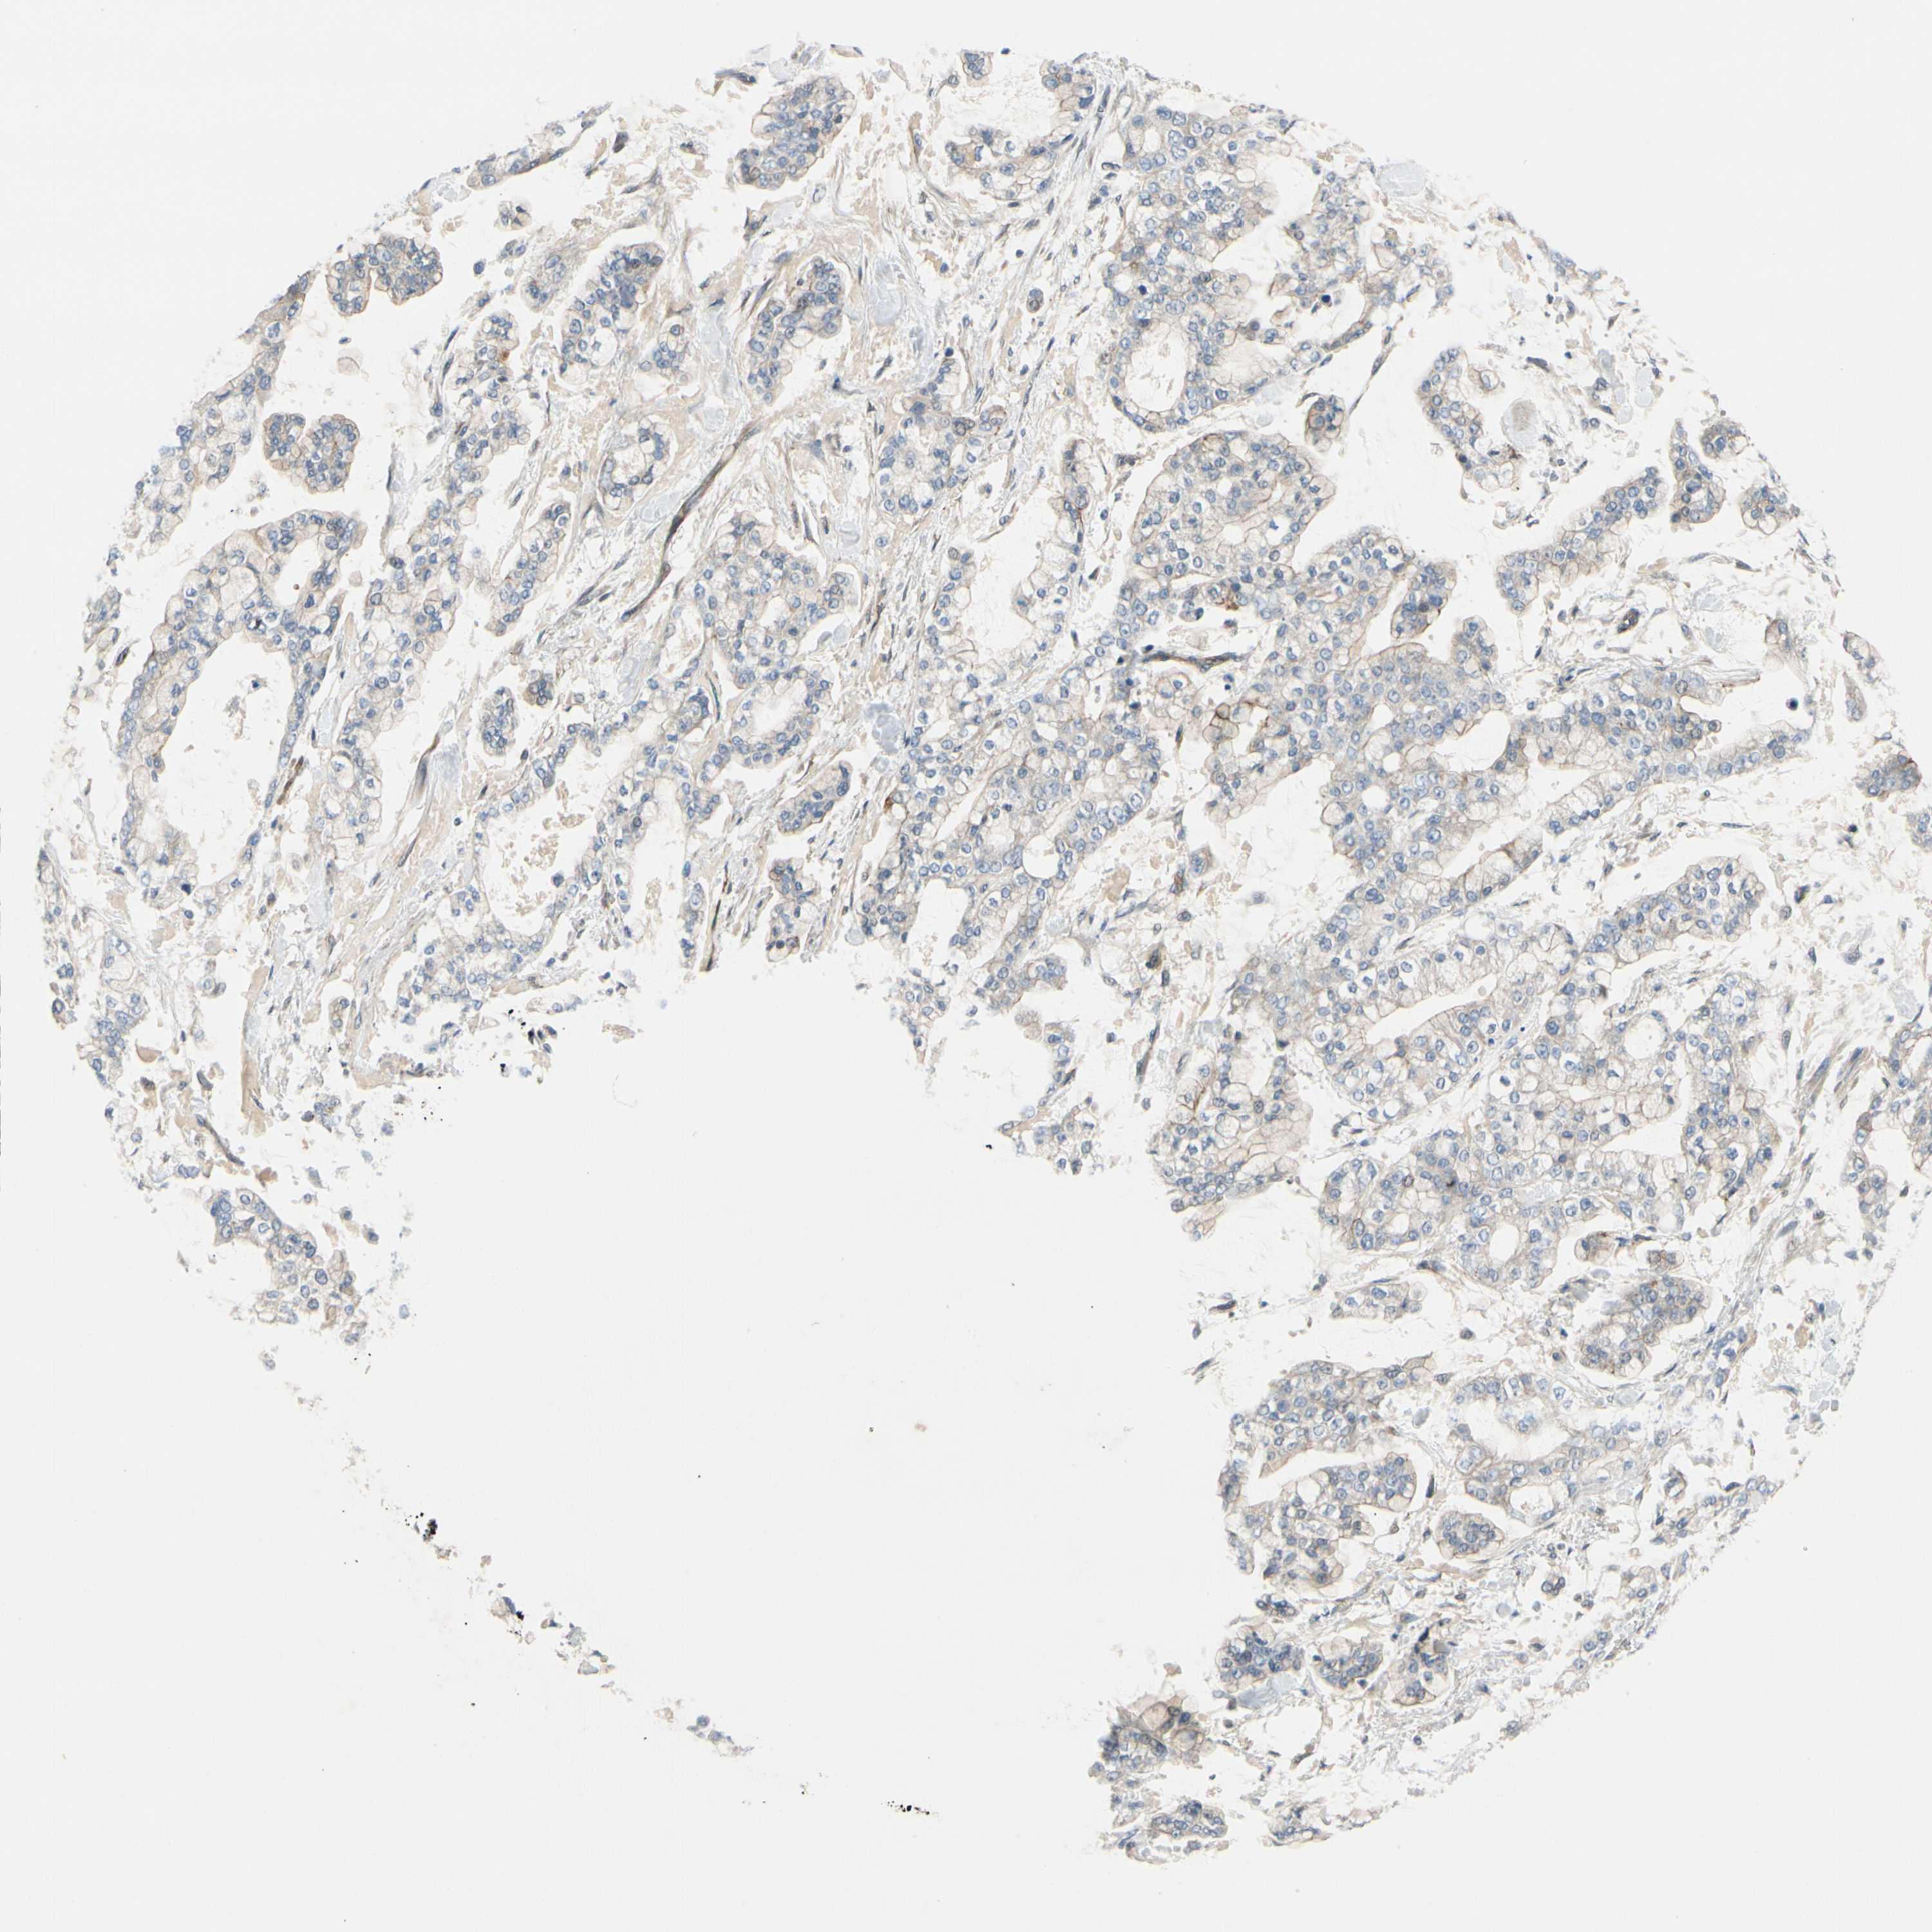

STOMACH CANCER - Protein expressioni

A mouse-over function shows sample information and annotation data. Click on an image to view it in a full screen mode. Samples can be filtered based on level of antibody staining by selecting one or several of the following categories: high, medium, low and not detected. The assay and annotation is described here.

Note that samples used for immunohistochemistry by the Human Protein Atlas do not correspond to samples in the TCGA dataset.

Antibody stainingi

Antibody staining in the annotated cell types in the current human tissue is reported as not detected, low, medium, or high, based on conventional immunohistochemistry profiling in selected tissues. This score is based on the combination of the staining intensity and fraction of stained cells.

Each image is clickable and will lead to virtual microscopy that enables deeper exploration of all samples and also displays staining intensity scores, fraction scores and subcellular localization as well as patient and tissue information for each sample.

Antibody HPA008233

Staining

High

Medium

Low

Not detected

Intensity

Strong

Moderate

Weak

Negative

Quantity

>75%

75%-25%

<25%

None

Location

Nuclear

Cytoplasmic/membranous

Cytoplasmic/membranous,nuclear

Adenocarcinoma, NOS